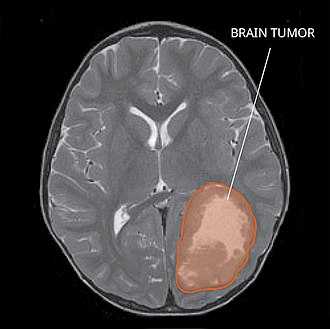

Для определения наличия заболевания можно использовать несколько анализов. Физические осмотры, показывающие отек диска зрительного нерва, дефекты поля зрения, черепные нервы паралич, дисфазия и очаговые неврологические нарушения являются свидетельством возможной опухоли. [2] PNET также можно обнаружить через компьютерная томография (CT) и магнитно-резонансная томография (МРТ). [2] В изображениях, созданных МРТ, нерегулярное увеличение твердой массы будет указывать на наличие опухоли. [3] Однако результаты МРТ обычно неоднозначны при определении наличия этой конкретной опухоли. [2] В Компьютерная томография, наличие PNET будет обозначаться повышенной плотностью и увеличением объема мозга. [2] В компьютерная томография может также показать кальцификация, [3] который присутствует в 41-44% случаев PNET. [2] Поскольку опухоль может воспроизводиться в других частях нервной системы через спинномозговая жидкость (CSF), также может быть проведен анализ CSF. [2] МРТ позвоночника - это четвертый тип анализа, который полезен при исследовании уровня распространения опухоли на спинной мозг. [2]

Имеющиеся на сегодняшний день методы диагностики нейроэктодермальных опухолей включают рентгенографию, гистологические исследования, биопсию, внутривенное контрастирование, компьютерную и магнитно-резонансную томографию, радиоизотопное сканирование. Эти и другие методы позволяют максимально точно определить первичную локализацию опухоли, обнаружить метастазы в мягких костных тканях, а также в лимфатических сосудах и ликворопроводящих путях. Магнитно-резонансная томография дает возможность наиболее подробно изучить мягкие ткани, костный и головной мозг. С помощью МРТ нередко удается выявить самые мелкие очаги нейроэктодермальных новообразований, что особенно важно для благоприятного прогноза заболевания.